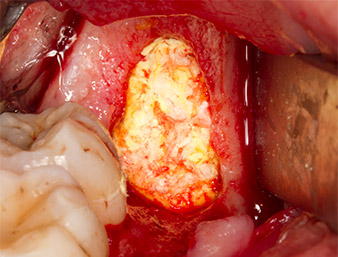

Per ottenere materiale autogeno per il successivo trattamento della ferita, sono stati estratti frammenti di osso sano nella zona del residuo di radice con uno strumento piezochirurgico (Piezomed B5) (Fig. 5).

Il tessuto autogeno è stato rimosso con la sezione a forma di raschietto della parte funzionante dello strumento e conservato un una soluzione salina fisiologica per uso successivo (vedere Fig. 13).